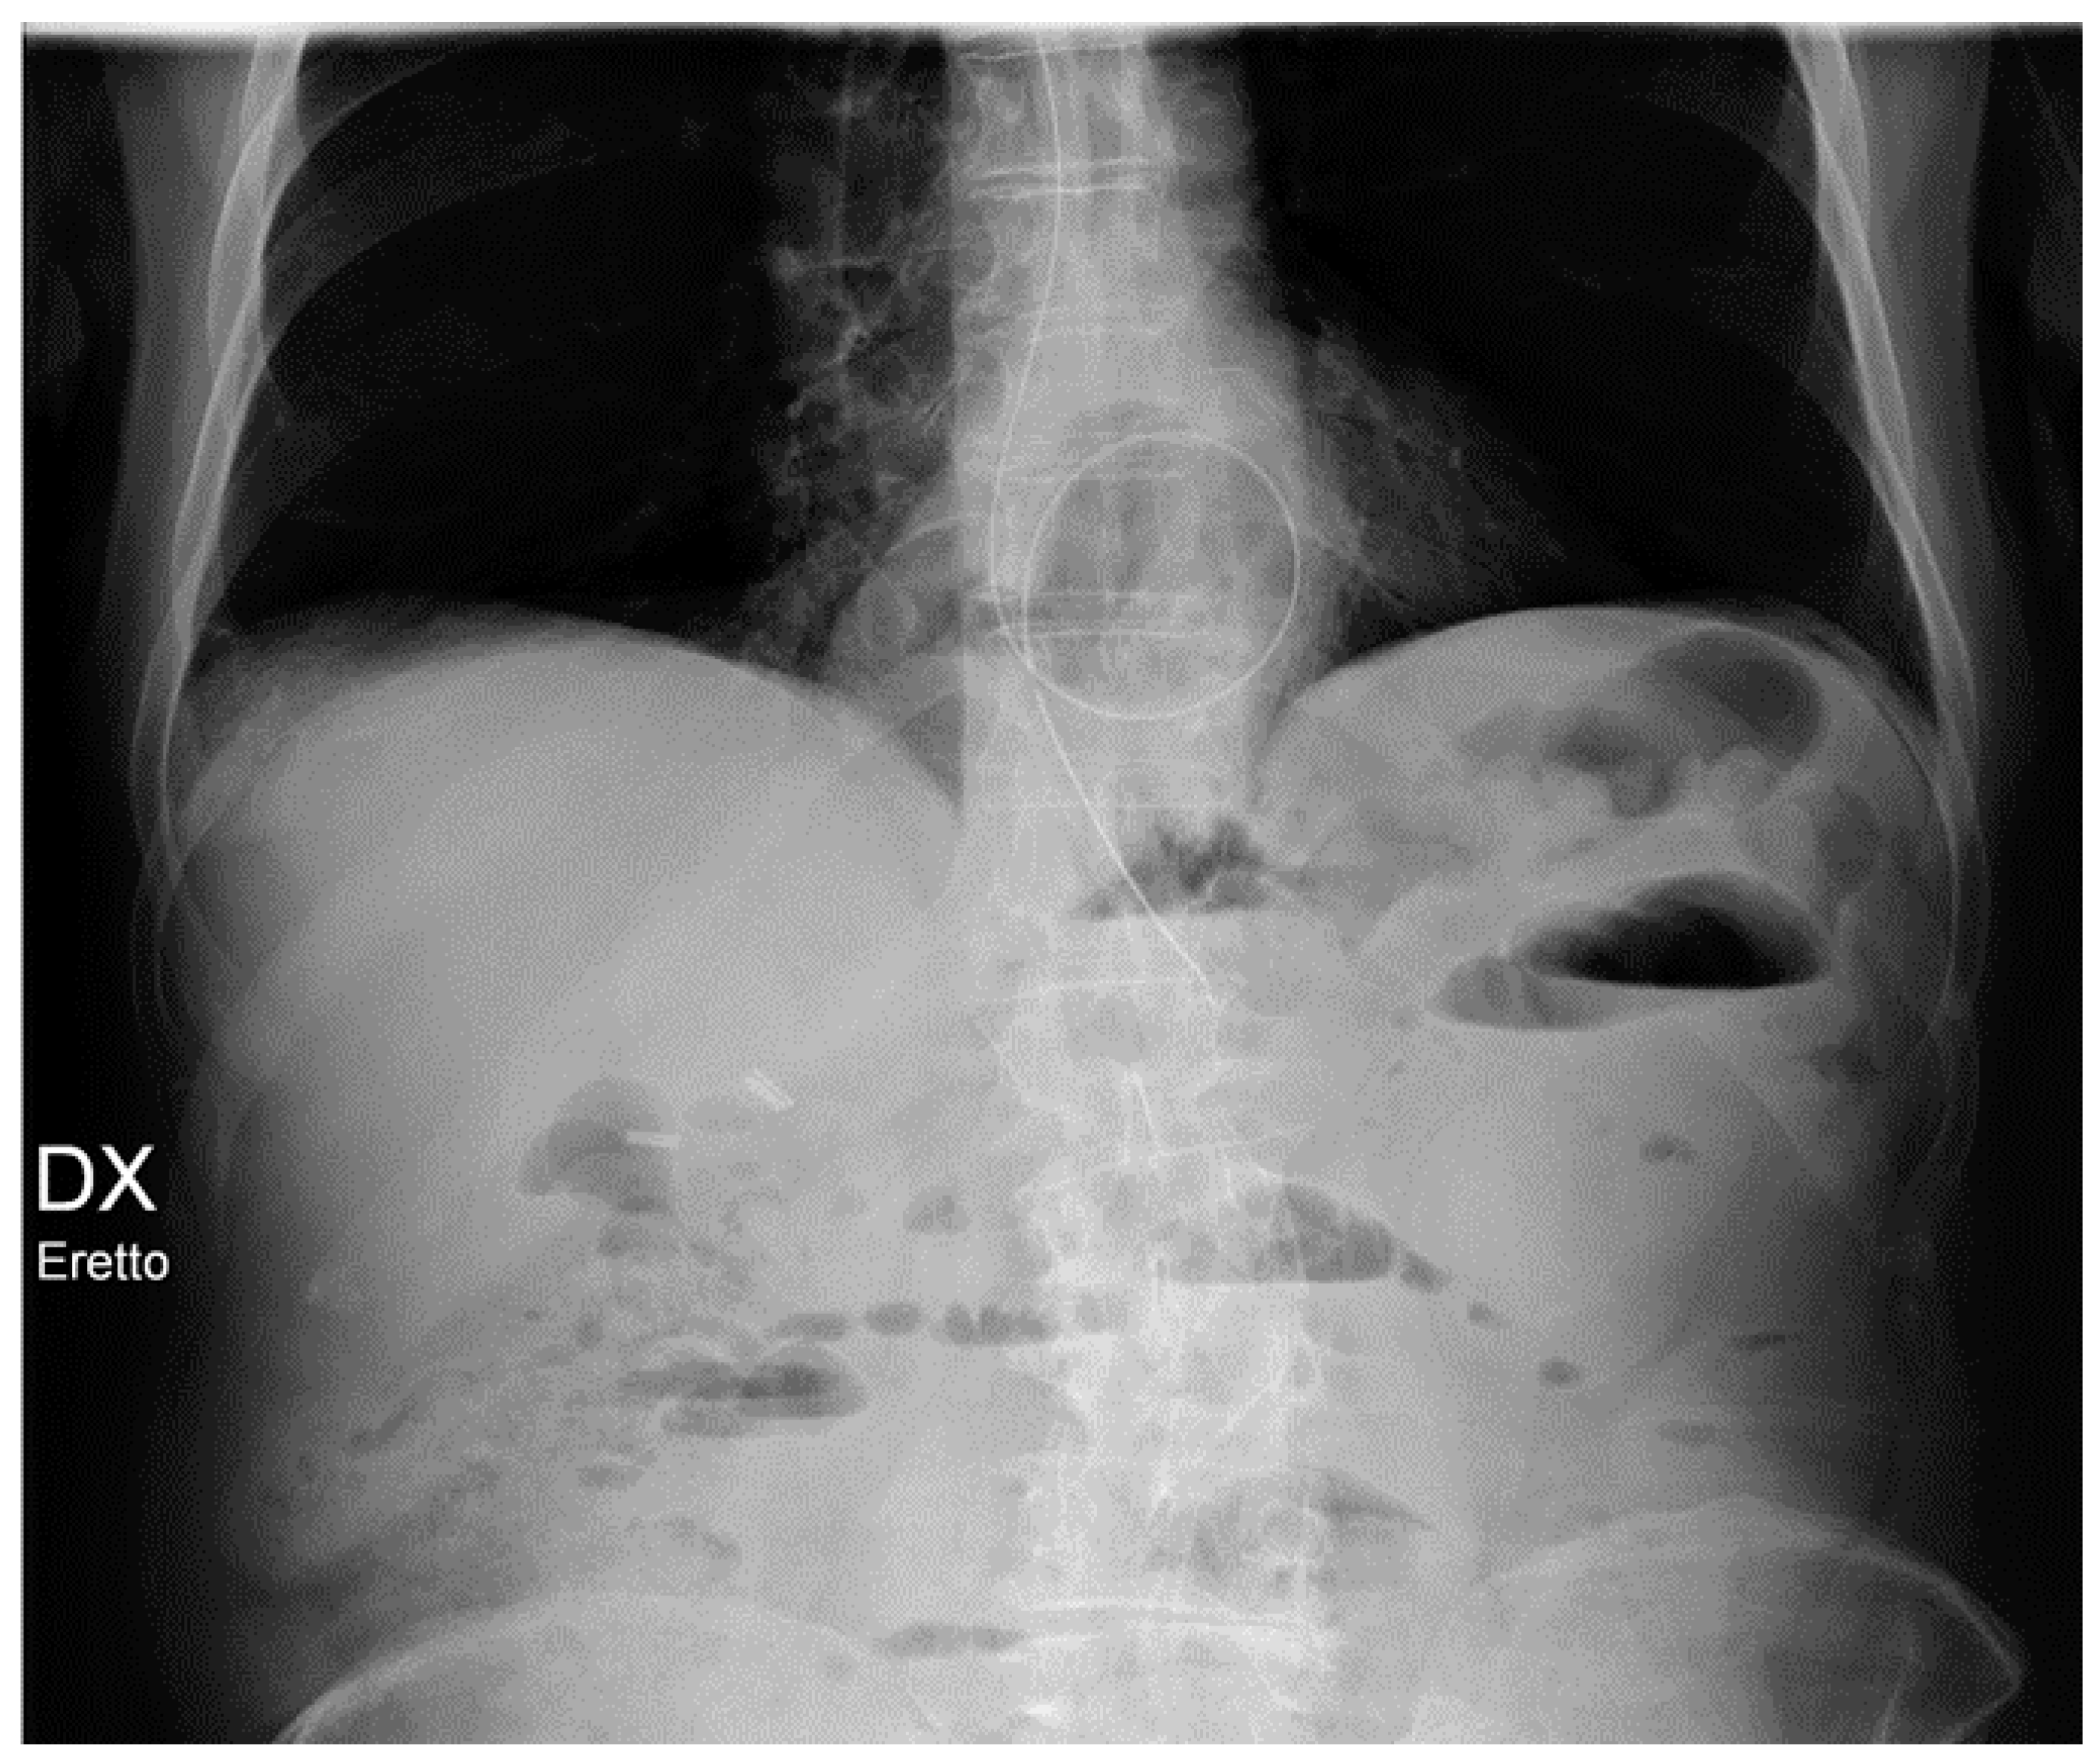

An IAPB catheter is radiolucent, except for two radiopaque marks at both endings to allow for its identification on CXR. The ideal positioning of the IABP should be at the level of the descending aorta, below the origin of the left subclavian artery and above the splanchnic vessels, to avoid complications such as the occlusion of these vessels or losing of device functionality. On a CXR, an IABP should be at the aortopulmonary level (Figure 17).

Figure 17.

Malpositioned IABP. (a) Anteroposterior CXR of a patient with an IAPB placed too distal from the aortic arch: the upper radiopaque mark can be seen at the level of the sixth intercostal space (red circle). (b) The same patient after repositioning of the IABP, with the upper mark now just under the aortic arch, in the proximal thoracic descending aorta, at the level of the fourth intercostal space (green circle).

The main complications of IABPs include aortic dissection and malpositioning. The CXR has a role in diagnosing mainly the latter, the first complication being a clinical emergency that needs an emergency CT angiography (Table 4) [30].